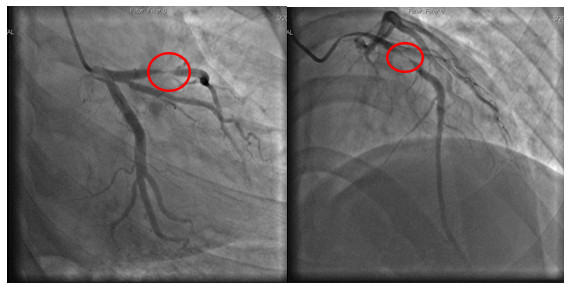

| Hình ảnh phim chụp thể hiện động mạch bị tắc - Ảnh BVCC |

Tại Bệnh viện Đa khoa tỉnh Phú Thọ, người bệnh được làm các xét nghiệm, điện tâm đồ, siêu âm tim và được chẩn đoán nhồi máu cơ tim cấp. Các bác sĩ đã chỉ định chụp và can thiệp động mạch vành qua da. Kết quả chụp mạch vành cho thấy hẹp 99% LAD1, ngay lập tức người bệnh được can thiệp nong bóng, đặt một stent tại vị trí động mạch bị tắc để tái thông dòng chảy.